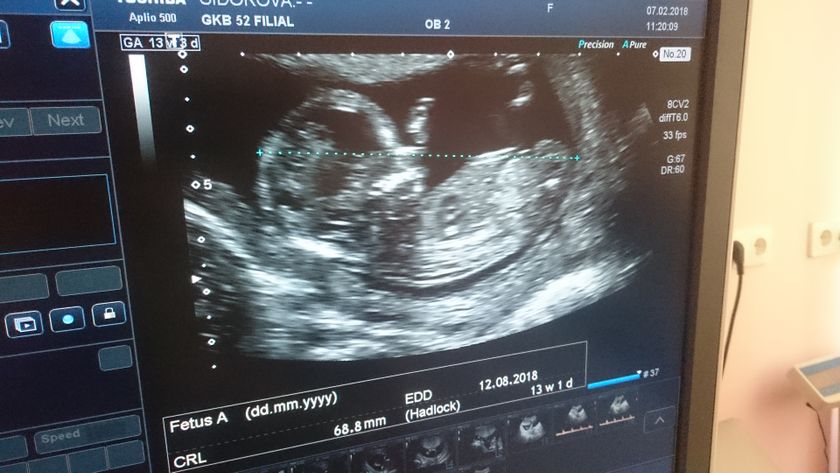

Ураа, прошёл первый долгожданный скрининг. Легла на кушетку, врач говорит «беременность развивается, сердечко бьётся, сейчас всё сама посмотрю и вам покажу» и молчание минут на 10… и вождение датчиком по животу. Повернула ко мне монитор, а там малыш дрыгает ногами и руками ? в итоге всё в норме, никаких отклонейни, больше мне ничего не сказали, благо разрешили сделать фотографию с экрана ? По ощущениям будто я не беременна ? не тошнило, не на что не тянет, вес -1кг